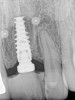

Figure 11  Postoperative PA radiograph, patient in Figure 8 through Figure 10.

Figure 11